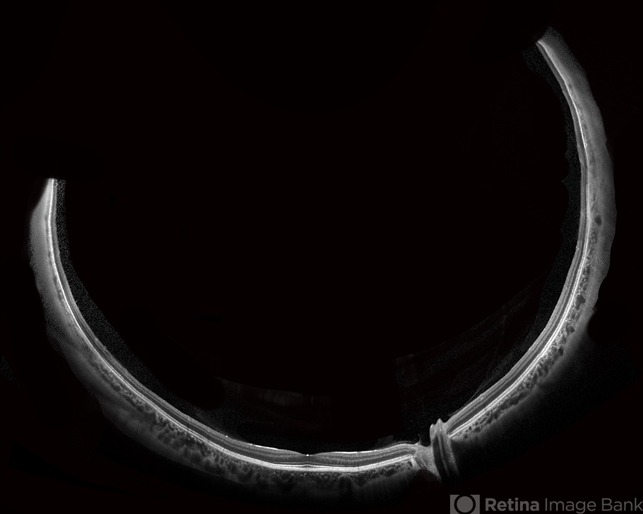

Optical coherence tomography system

Heidelberg Spectralis OCT system - Description

- This is an SD-OCT montage image of a 55 year old male with optic neuropathy representing a wide-field OCT spanning 130 degrees.